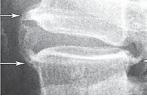

Рентгенограмма № 4

Форма и размеры спондилёза обусловлены размерами выпячивания межпозвонкового диска. Скорость компенсации, то есть развития спондилёза, напрямую зависит от активности шарпеевских волокон. Различают три стадии развития спондилёза. Первая — это когда краевые костные разрастания не выходят за площадь выпятившегося межпозвонкового диска. Вторая стадия — когда костные наросты выходят за пределы площади выпятившего межпозвонкового диска и огибают его. И третья стадия, резко выраженный спондилёз, когда такие костные наросты растут навстречу друг другу, а затем сращиваются вместе, образуя единый оссификат (лат. os, ossis — кость, facio — делать; окостенение), блокирующий движение в соответствующем позвоночно-двигательном сегменте. То есть, образуется своеобразная мощная костная скоба, которая соединяет тела смежных позвонков и жёстко фиксирует сегмент.

Костные разрастания и высота межпозвонкового промежутка косвенно указывают на процессы, которые происходят в межпозвонковом диске, что подтверждается при сравнении рентгенологических и МРТ обследований.